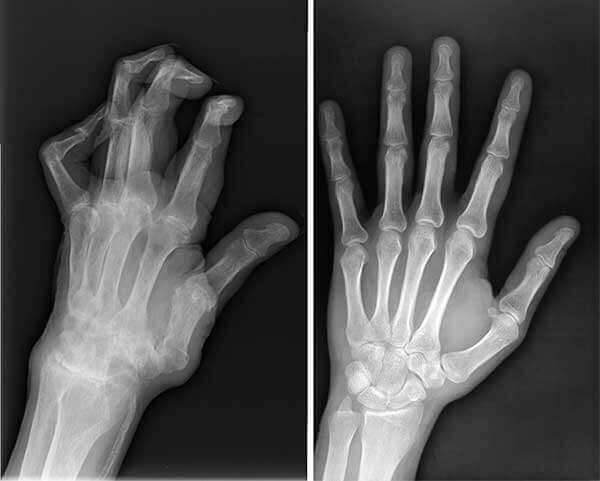

The condition of my knee at that time. Severe pain.

At the appointment, the doctor looked at the pictures for a long time and said that I should no longer do physical labor. And he forbade me to lift anything heavier than 2 kg.

X-rays showed serious problems with my knee.

And this is what my healthy knee looks like now.

X-ray of husband before and after taking EasyGO.

My husband's hands before and after taking EasyGO.